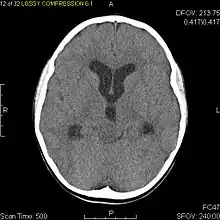

Usually – depending on the interview of the patient and after a clinical exam which includes a neurological exam and an ophthalmological exam – a CT scan and/or an MRI scan will be performed to confirm the presence of a tumor. They are usually easily distinguishable from normal brain structures using these imaging techniques. A special dye may be injected into a vein before these scans to provide contrast and make tumors easier to identify. Pilocytic astrocytomas are typically clearly visible on such scans, but it is often difficult to say based on imaging alone what type of tumor is present.